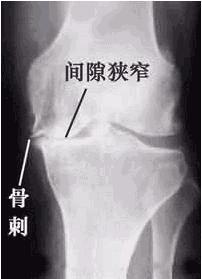

所謂骨質增生,是指關節軟骨的改變,主要有椎骨邊緣或關節邊緣,關節面及骨實處骨小梁增多和骨密度增高或骨質

疏鬆。因有時其增生形成狀象口唇或象鳥嘴等,故叫做唇狀突起或骨贅,一般人稱之為骨刺。骨贅的組織學檢查,完全為正常組織無任何病理改變,所以稱之為老年性退行性關節病,又稱骨關節病。骨性關節炎,增生性關節炎,肥大性關節炎和中醫所稱的“骨痹”等統稱骨質增生。好發於負重大,活動多的關節,如:頸、腰、胸椎、膝、手指、腳跟等處。